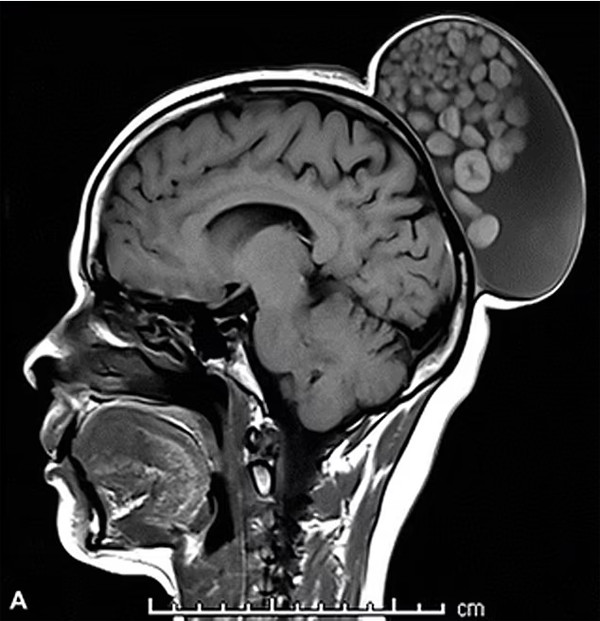

Công bố bức ảnh về khối u trên Radiology, bệnh viện cho biết, các mô phát triển bất thường trong u nang có kích thước khác nhau và giống như một túi sỏi. Viện Khoa học Y tế Cao cấp Sri Sathya Sai nhận định dạng bệnh này không phổ biến. Chụp cộng hưởng từ cho thấy khối u dài 15cm, rộng 10cm và cao 12cm.

Sau khi phẫu thuật cắt bỏ, ê-kíp ghi nhận, u nang chứa các phân tử giống như chất béo, các khối cầu chất sừng (loại protein giúp hình thành tóc, móng tay, lớp ngoài của da) và tóc trôi nổi trong chất dịch.

Kiểm tra bằng kính hiển vi xác nhận đó là u nang da - một dạng u quái nang trưởng thành. Bệnh nhân được theo dõi suốt 6 tháng sau khi loại bỏ khối u. Bà không bị tái phát trong giai đoạn này.